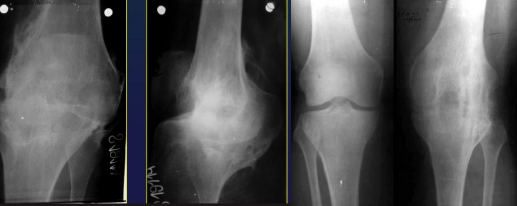

Knee

Gonarthrosis

Hip

Coxarthrosis

Hand

Polyarthrosis (DIPh, Trapezo MC1)

Arthrosis Rx

GENERAL Rx signs

Joint space narrowing (even or uneven)

Subchondral OS

Subchondral cysts

Osteophytes